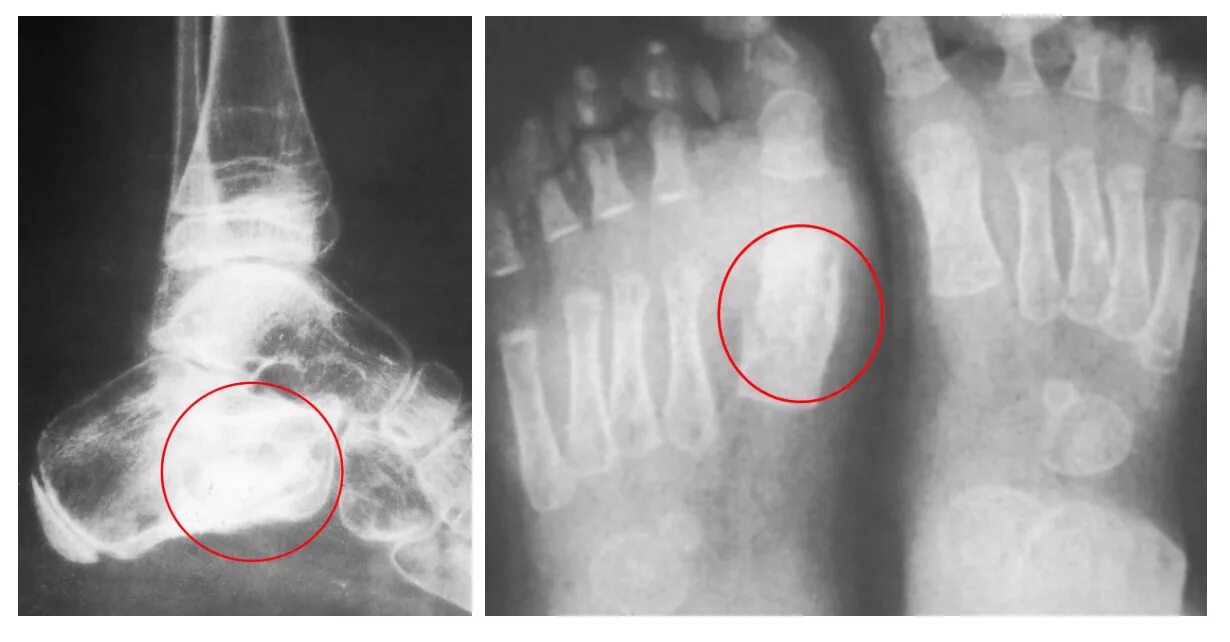

Туберкулез суставов симптомы